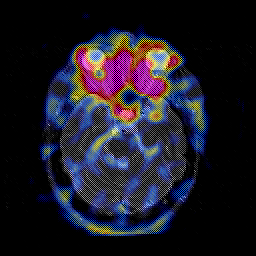

Glioblastoma multiforme overlay -- Slice #19

[Home][Help][Clinical][Tour 1][Tour 2][Tour 3] Slice 19